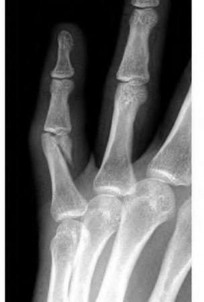

Question 13:

A 40-year-old diabetic male presents with a swollen, painful right index finger after a puncture wound. You suspect pyogenic flexor tenosynovitis. Kanavel's classical cardinal signs for this condition include all of the following EXCEPT:

Options:

- Fusiform swelling of the entire digit

- Pain with passive extension of the digit

- Flexed resting posture of the digit

- Erythema extending proximally into the mid-palm

- Tenderness to palpation along the flexor tendon sheath

Correct Answer: Erythema extending proximally into the mid-palm

Explanation:

Kanavel's four cardinal signs of flexor tenosynovitis are: 1) fusiform (sausage-like) swelling of the digit, 2) severe pain with passive extension, 3) a flexed resting posture of the digit, and 4) tenderness along the entire course of the flexor tendon sheath. Erythema extending to the mid-palm is not one of Kanavel's specific signs, though localized erythema may be present.